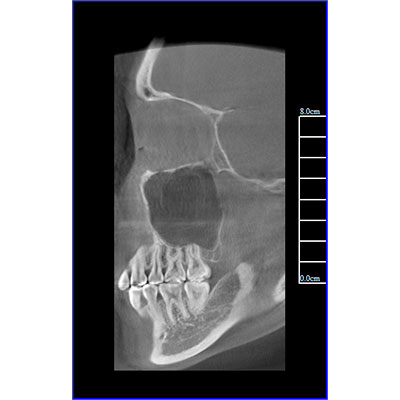

該款牙科CBCT產(chǎn)品采用動(dòng)態(tài)平板探測器,獲得三維圖像的同時(shí)還具有數(shù)字化全景功能,廣泛應(yīng)用于口腔頜面外科、正畸科、正頜外科、種植科、牙體科、顳下頜關(guān)節(jié)科等術(shù)前術(shù)后。

專有三維重建算法,可提供任意位置高清斷層影像。

可同時(shí)觀察軸向面、冠狀面和矢狀面圖像,方便臨床診斷。